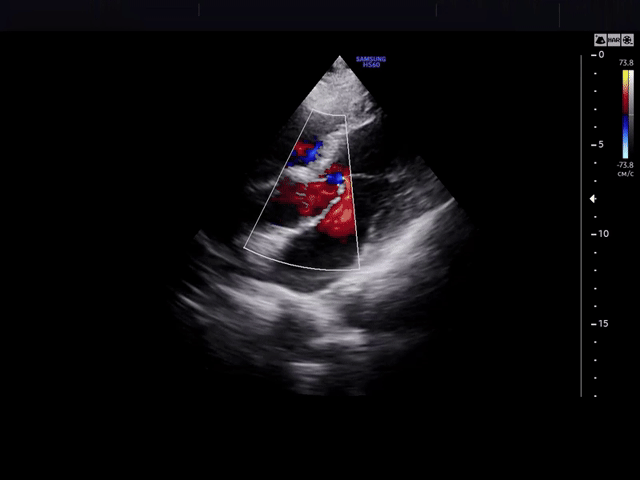

Метод основан на способности ультразвука отражаться от структур сердца, имеющих разную плотность. Современная эхокардиография — это мультипараметрическое исследование. Оно включает в себя не только визуализацию в В-режиме (серая шкала), но и обязательное использование допплерографических методик (цветное, импульсно-волновое, непрерывно-волновое картирование) для оценки внутрисердечной гемодинамики. Сегодня ЭхоКГ позволяет неинвазивно и с высокой точностью выявить патологию на ранних стадиях, когда клинические симптомы могут еще отсутствовать.

В РНПЦ исследование проводится на аппаратах экспертного класса (например, GE Logiq, Esaote MyLab или аналогичных), оснащенных специализированными кардиологическими датчиками и пакетами программ для углубленного анализа. Аппаратура позволяет проводить исследование в стандартных режимах (М-режим, 2D-режим) и всех режимах допплера (спектральный, цветовой, тканевой).